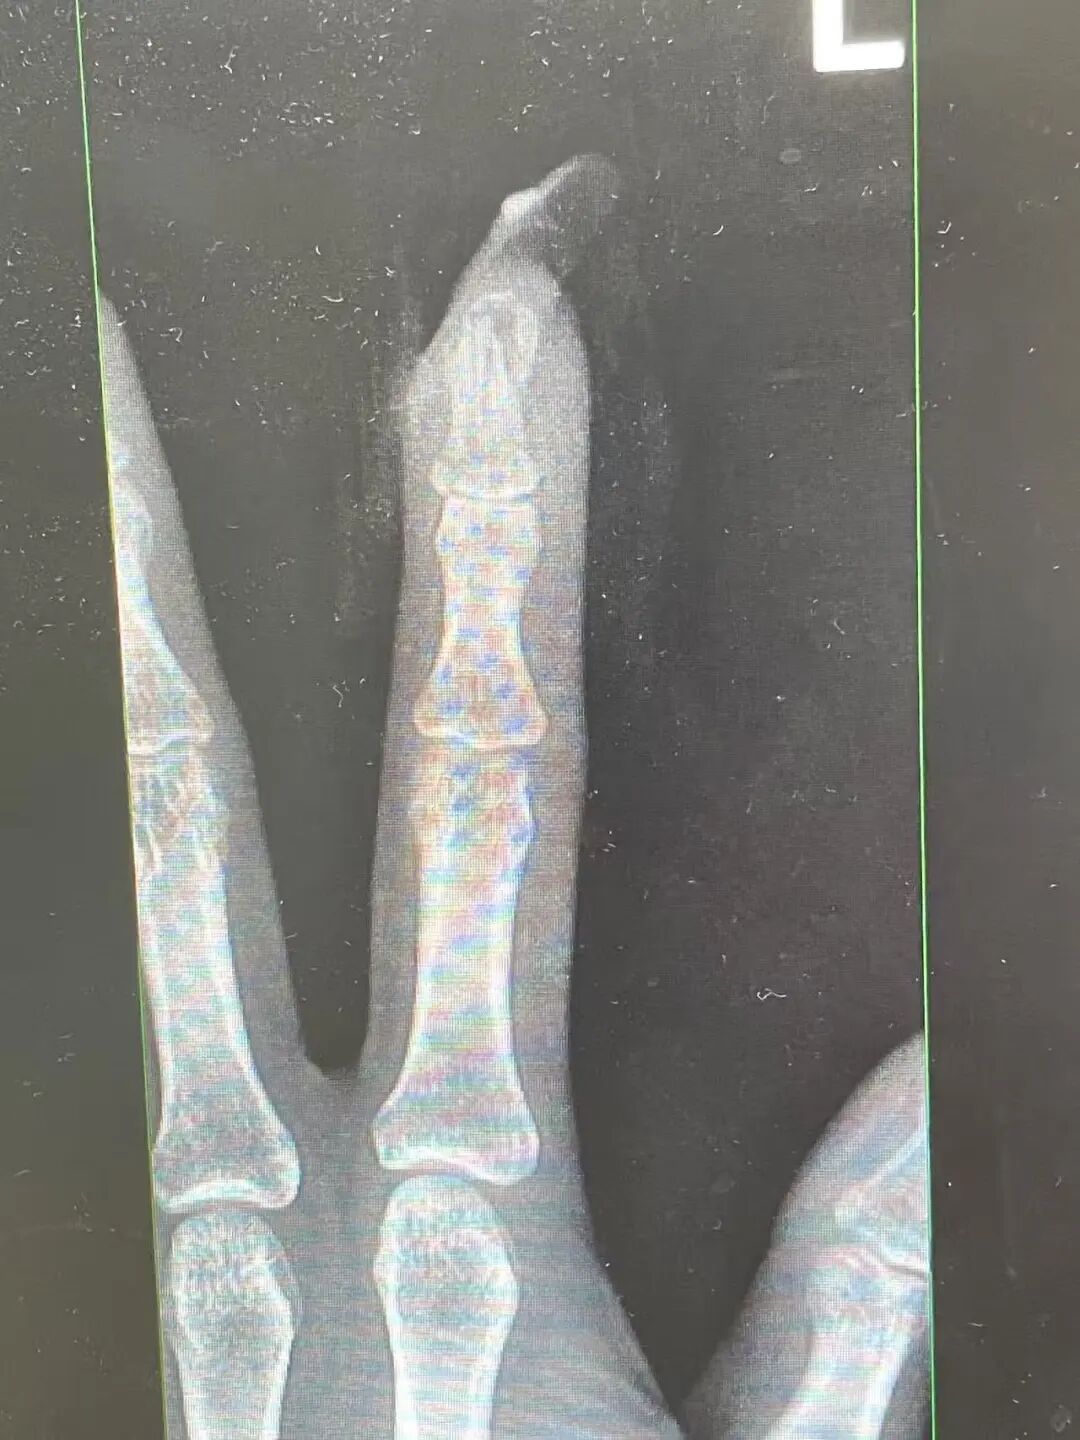

“食指指骨骨折,甲床破裂。”接诊的骨科医生曹立检查后发现王女士指甲断裂,部分甲床外露,需要手术修复。曹医生立刻为王女士进行指骨骨折闭合复位内固定术,术后恢复良好。曹医生表示,如果没有美甲,伤害不会这么严重。